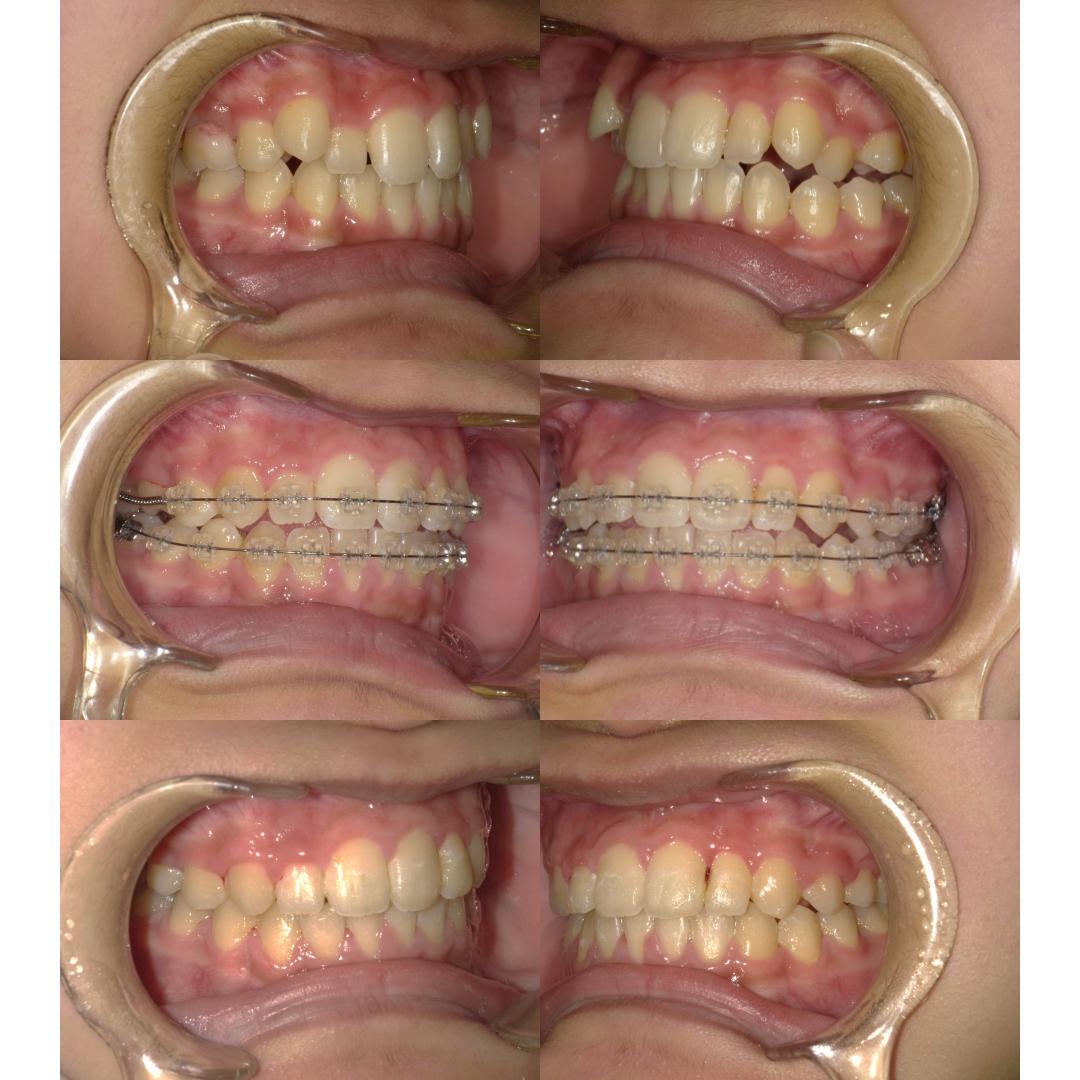

現在、歯列不正になる原因は、下顎の位置関係、歯の傾きなど様々な要因があることがわかっています。

そういった様々な要因を取り除くことで、従来、小臼歯(4番、5番)を抜歯しなければ治療できない症例でも、非抜歯で治療可能となってきているのです。

また、下顎の位置関係、歯の傾きなどの原因を新素材ゴムメタルワイヤーで治療を行うことでほとんどの症例で小臼歯を抜歯しなくても治療可能になってきています。